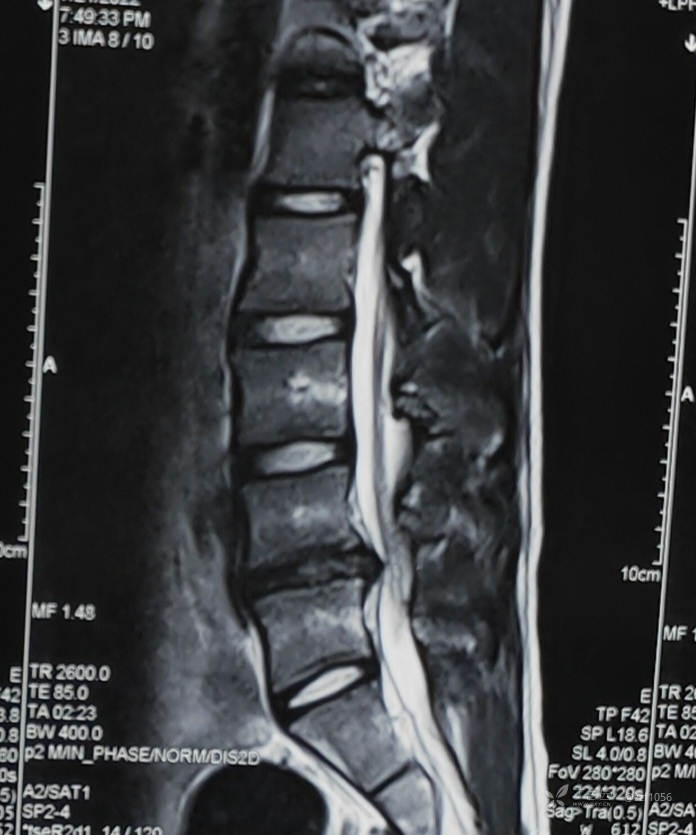

患者男,19岁,高三学生,左下肢疼痛半年,各种保守治疗无效

体育特长生,平时举杠铃蹲卧训练,平素体健

入院诊断:腰椎间盘突出症(L4/5)

虽然能够选择性微创,年轻化与复发也是个问题